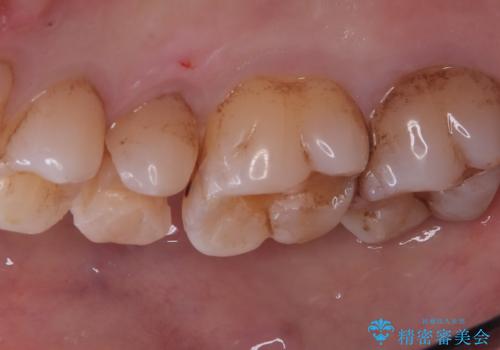

右上5番にう蝕があり、審美性・適合性・材料安定性の高いセラミックインレーでのやり替えとなりました。

右上5番の近遠心にう蝕が認められたため、CR裏層の後MOD窩洞のセラミックインレーとしました。

インレーセット時はラバーダム防湿を行っています。